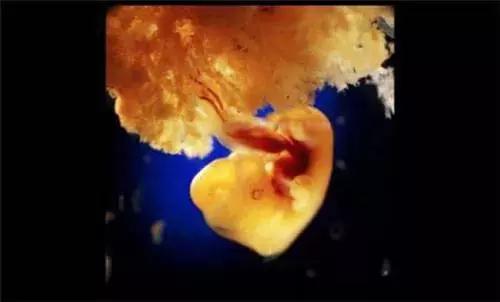

22天后,胚胎发育

胎儿的心脏

受精后第28天